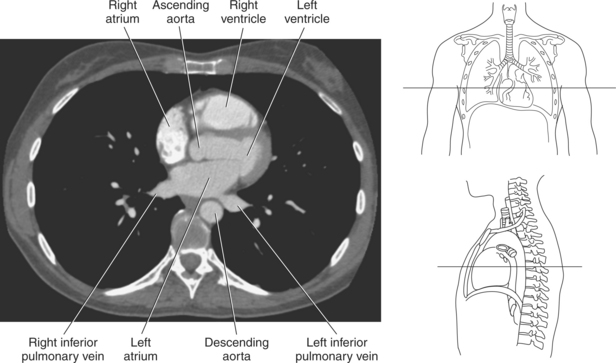

The heart is a hollow, four-chambered muscular organ located within the middle mediastinum. It is approximately the size of a large clenched fist and is situated obliquely in the chest with one third of its mass lying to the right of the median plane and two thirds to the left. The heart can be described as being roughly trapezoid shaped (Figure 6.33). The superficial relationships of the heart include the base, apex, three surfaces (sternocostal, diaphragmatic, pulmonary), and four borders (right, inferior, left, and superior). The broad base (posterior aspect) is the most superior and posterior portion of the heart. It is formed by both atria, primarily the left atrium, and gives rise to the great vessels. The apex is formed by the left ventricle and points inferiorly, anteriorly, and to the left. It is located at the level of the fifth intercostal space, just medial to the midclavicular line. The sternocostal (anterior surface) is formed primarily by the right atrium and right ventricle with a small contribution from the left ventricle. The diaphragmatic (inferior surface) rests on the central tendon of the diaphragm and is formed by both ventricles and a small portion of the right atrium. The pulmonary (left surface) is formed mainly by the left ventricle and fills the cardiac notch of the left lung. The borders of the heart represent the external surfaces of the cardiovascular silhouette in radiographic profile. The borders include the right border, formed by the right atrium and located between the superior and inferior venae cavae; the left border, formed by the apex of the heart or the left ventricle; the superior border, formed by the right and left atria; and the inferior border, which is formed primarily by the right ventricle with a small contribution from the left ventricle (Figures 6.33 through 6.35).

The walls of the heart consist of three layers: (1) epicardium, the thin outer layer that is in contact with the pericardium; (2) myocardium, the thick middle layer consisting of strong cardiac muscle; and (3) endocardium, the thin, endothelial layer lining the inner surface. The endothelial layer also lines the valves of the heart and is continuous with the inner lining of the blood vessels. The heart is divided into four chambers: the right and left atria and the right and left ventricles. The two superior collecting chambers called atria are divided by the interatrial septum. During embryonic development an oval opening exists within the interatrial septum called the foramen ovale. This opening allows blood flow between the right and left atria during fetal lung development. At birth, the foramen ovale closes, leaving a small depression in the septal wall called the fossa ovalis in the adult heart. The two inferior pumping chambers called ventricles are divided by the interventricular septum (Figure 6.39).

The right atrium forms the right border of the heart and receives deoxygenated blood from the body via the superior and inferior venae cavae and from the coronary sinus and cardiac veins that drain the myocardium. A small muscular embryonic appendage, the right auricle, projects upward and toward the left from the right atrium, covering the root of the aorta (Figure 6.40). The right ventricle lies on the diaphragm and comprises the largest portion of the anterior surface of the heart. It receives deoxygenated blood from the right atrium and forces it into the pulmonary trunk for conveyance to the lungs. Projecting off the inferior surface of the ventricular walls are conical-shaped projections of cardiac muscle called papillary muscles that anchor the cusps of the tricuspid valve to the right ventricle (Figure 6.39). The left atrium lies posterior to the right atrium and is the most posterior surface of the heart. It also has an embryonic appendage, the left auricle, that projects to the left of the pulmonary trunk over the superior surface of the heart. The left atrium receives oxygenated blood directly from the lungs via the four pulmonary veins (two on each side). The left ventricle forms the apex, left border, and most of the inferior surface of the heart. It receives oxygenated blood from the left atrium and pumps it into the aorta for distribution throughout the systemic circuit. The myocardium of the left ventricle is normally three times thicker than that of the right ventricle, reflecting the force necessary to pump blood to the distant sites of the systemic circulation (Figures 6.41 through 6.52). Two papillary muscles project from the ventricular walls to anchor the bicuspid valve to the ventricle (Figures 6.39 and 6.47).

Blood travels to and from the heart through the great vessels, which include the aorta, pulmonary arteries and veins, and superior and inferior venae cavae (Figures 6.54 and 6.55). The aorta is the largest artery of the body and can be divided into the ascending aorta, aortic arch, and descending aorta. The ascending aorta begins at the base of the left ventricle at the level of the sternal angle, then curves superiorly and posteriorly as the aortic arch over the root of the left lung. The top of the aortic arch is approximately at T3 (Figures 6.56 and 6.57). The arch continues as the descending aorta posterior to the left bronchus and pulmonary trunk, on the left side of the vertebral body of T4 (Figures 6.58 and 6.59). The descending aorta passes slightly anterior and to the left of the vertebral column as it descends through the thoracic and abdominal cavities (Figure 6.60). While in the thoracic cavity, the descending aorta is commonly called the thoracic aorta, and while in the abdominal cavity, it is called the abdominal aorta. The pulmonary trunk is the origin of the right and left pulmonary arteries and lies entirely within the pericardial sac. It arises from the right ventricle and ascends in front of the ascending aorta, courses posteriorly and to the left, where it bifurcates at the level of the sternal angle (T4) into the right and left pulmonary arteries (Figures 6.61 through 6.63). The pulmonary trunk is attached to the aortic arch by a fibrous cord called the ligamentum arteriosum, the remnant of an important fetal blood vessel (ductus arteriosus) that links the pulmonary and systemic circuits during fetal development (Figures 6.54 and 6.61). The right pulmonary artery courses laterally, posterior to the ascending aorta and superior vena cava, and anterior to the esophagus and right mainstem bronchus, to the hilum of the right lung. At the root of the right lung, the right pulmonary artery divides into two branches, with the lower branch supplying the middle and inferior lobes and the upper branch supplying the superior lobe (Figures 6.61 through 6.64). The left pulmonary artery, shorter and smaller than the right, is also the most superior of the pulmonary vessels. It travels horizontally, arching over the left mainstem bronchus, and enters the hilum of the left lung just superior to the left mainstem bronchus (Figures 6.61 through 6.64). Within the lungs, each pulmonary artery descends posterolateral to the main bronchus and divides into lobar and segmental arteries, continuing to branch out and to follow along with the smallest divisions of the bronchial tree (Figures 6.61 and 6.64). Located inferior to the pulmonary arteries are the four pulmonary veins, two each (superior and inferior) extending from each lung to enter the left atrium (Figures 6.54, 6.55, 6.61, and 6.64 through 6.68). They commence in a capillary network along the walls of the alveoli, where they are continuous with the capillaries of the pulmonary arteries. The venous capillaries merge to form small vessels that unite successively to eventually form a single trunk for each lobe: three for the right and two for the left lung. Frequently the trunk from the middle lobe of the right lung unites with the trunk from the upper lobe, forming just two trunks on the right side prior to entering the left atrium. The right superior pulmonary vein collects blood from the upper lobe segments of the right lung and passes anterior and inferior to the right pulmonary artery, behind the superior vena cava. The right inferior pulmonary vein receives blood from the right lower lobes of the lung and crosses behind the right atrium to the left atrium (Figures 6.61 and 6.69 through 6.71). The left superior pulmonary vein receives blood from the left upper lobe of the left lung and courses anterior and inferior to the left main bronchus as it enters the left atrium. The left inferior pulmonary vein drains the inferior lobe of the left lung and passes toward the left atrium anterior to the bronchi (Figures 6.61 and 6.72 through 6.74). The pulmonary veins course more horizontally than the pulmonary arteries and are ultimately oriented toward the left atrium. At the root of the lungs, the pulmonary veins are anterior to the pulmonary arteries, which are anterior to the bronchus. While within the lungs, the branches of the pulmonary arteries are anterior to the bronchi, which are anterior to the pulmonary veins. The superior and inferior venae cavae are the largest veins of the body. The superior vena cava is formed by the junction of the brachiocephalic veins, posterior to the right first costal cartilage, and carries blood from the thorax, upper limbs, head, and neck (Figure 6.24). As it travels inferiorly, it is located posterior and lateral to the ascending aorta before entering the upper portion of the right atrium (Figures 6.54 through 6.59). The inferior vena cava is formed by the junction of the common iliac veins in the pelvis and ascends the abdomen to the right of the abdominal aorta and anterior to the vertebral column. It passes through the caval hiatus of the diaphragm and almost immediately enters the inferior portion of the right atrium (Figures 6.75 and 6.76).